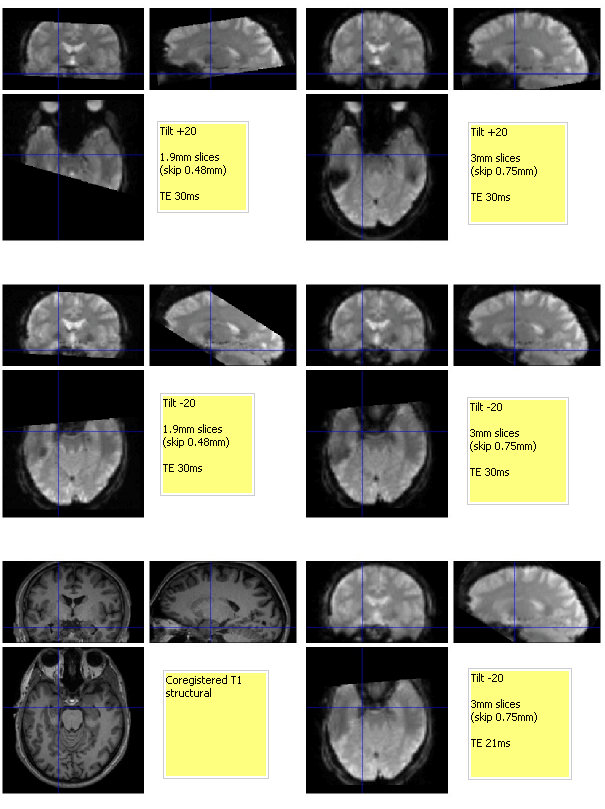

Attachment 'thicktiltTE.gif'